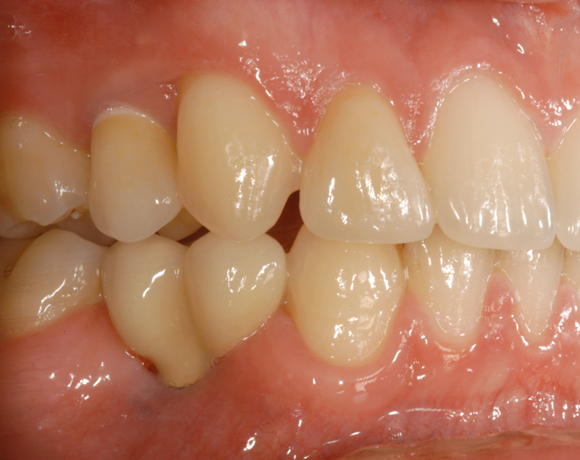

Bei dem letzten Patientenfall lagen Nichtanlagen der Zähne 12, 24, 34, 35, 44, 45 vor. Bei Zahn 12 schimmert das Implantat durch, es war sehr wenig Knochen vorhanden, aber das Ergebnis ist seit acht Jahren konstant gut. Zahn 22 lag als Zapfenzahn vor und wurde mit einem Veneer versorgt.